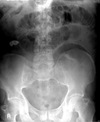

Small bowel obstruction

Large bowel obstruction

SBO vs LBO

Sigmoid vs caecal volvulus